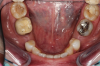

Fig 10. Preoperative panoramic radiograph.

Figure 10

Figure 10 through Figure 13 show the preoperative x-ray and the sequence of beginning with healed sites through the surgical placement of the implants. The implants were protected by an Essix-style wound-protection removable retainer for approximately 12 weeks. After the integration phase, the implants and the natural dentition were prepared using traditional crown-and-bridge high-speed diamond and zirconia cutting burs to remove decay and existing restorative materials, to complete and refine the natural-tooth structures to receive full-crown coverage, and to prepare and refine gingival margins of the zirconia implants where needed.